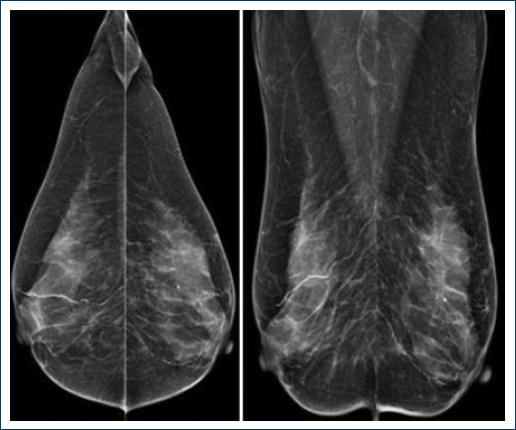

We report a 42-year-old woman with a long history of T1D with diabetic neuropathy. She came to our center because of an enlarging left breast mass. Clinical examination showed a left breast mass with nipple retraction. Mastography and ultrasound revealed a left breast BI-RADS-4c lesion (Figs. 3 and 4). Ultrasound-guided biopsy was performed, and after pathology study, DM was diagnosed.

Figure 3 Mammography: the breast is heterogeneously dense; there is an oval mass with obscured margin at the upper outer quadrant in the left breast.